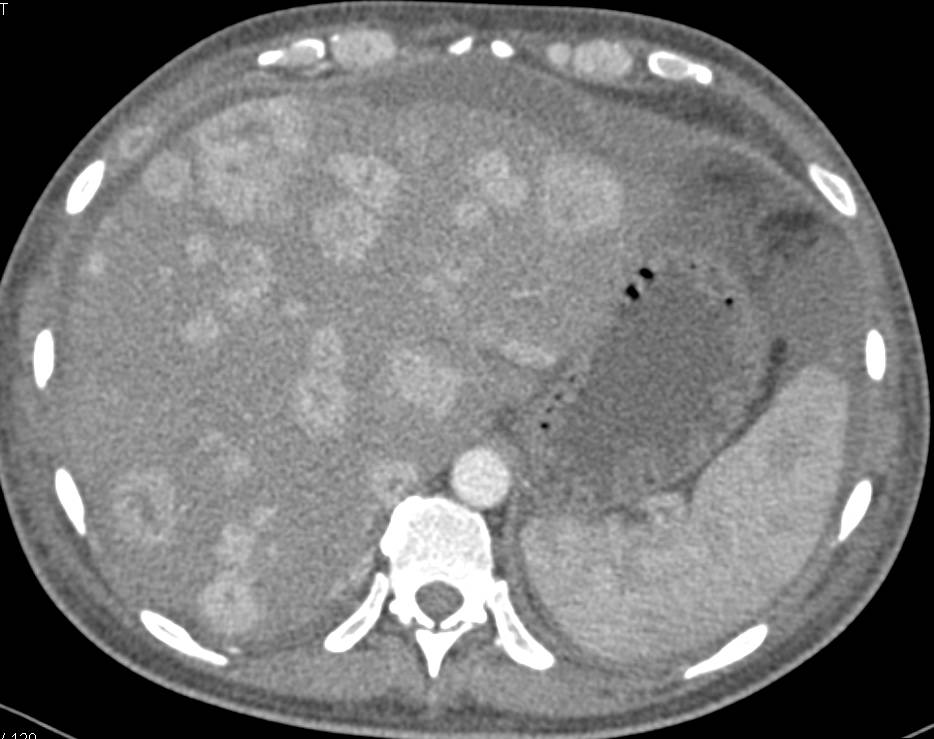

Pseudocyst Pushes Toward the Hilum of the Liver